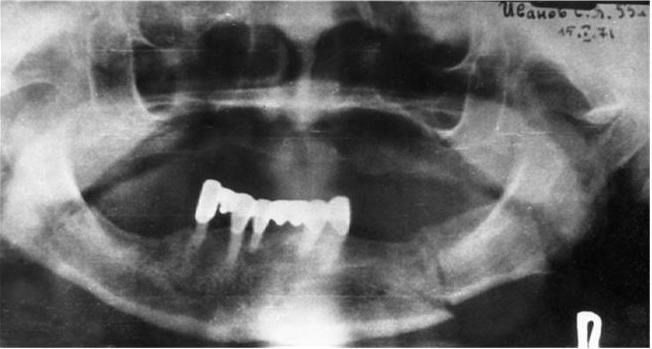

Используют также панорамную рентгенографию и, особенно, ортопантомографию нижней челюсти. Преимущество этого метода – возможность быстро получить ценную диагностическую информацию о состоянии зубов и нижней челюсти (при панорамной рентгенографии – особенно в переднем отделе челюсти).

Ортопантомографическое исследование позволяет на одном снимке проследить за изменениями, возникшими в результате перелома нижней челюсти на всем ее протяжении (рис. 5).

Рис. 5. Ортопантомограмма нижней челюсти при множественном переломе